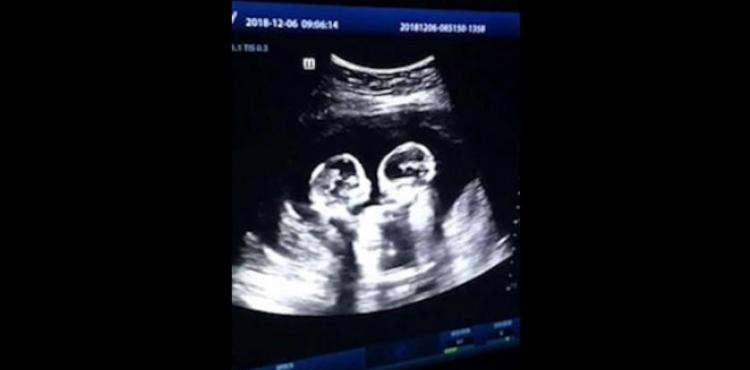

شاهد: عراك بالأيدي بين توأمين في بطن أمهما